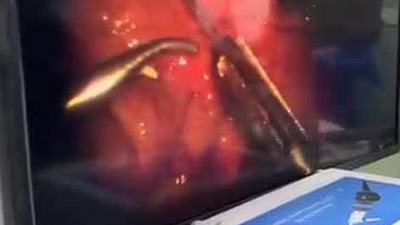

فريق طبي بمستشفى بنها التخصصي ينقذ حياة طفل ابتلع مسمار دباسة

إنجاز طبي جديد.. مؤسسة مرسال تعلن نجاح عملية استحثاث جذع المخ لطفلة 4 سنوات ضمن مشروع حكاية صوت

رمد المنصورة تنجح في إنقاذ عين صغيرة بعد إصابة قطعية معقّدة

جراح بعين شمس يتمكن من إنقاذ بصر رضيع حديث الولادة يعاني من ورم خلف العين

نجاح فريق طبي بمستشفى قها في إنقاذ شاب بعد إصابات خطيرة جراء حادث قطار

استخراج مسمار دباسة من بطن طفل في عملية نادرة بمستشفى الأطفال التخصصي ببنها

أطباء بنها ينقذون صغيرًا من عيب نادر بالقصبة الهوائية والمريء

نجاح إجراء عمليتين جراحيتين معقدتين بمستشفى دكرنس العام باستخدام جهاز C-ARM

جراحة دقيقة تنقذ شابًا من الموت بعد إصابة خطيرة في المخ بمستشفى ميت غمر

إنجاز طبي بمستشفى القصاصين التخصصي.. نجاح أول جراحة لاستئصال ورم بالغدة النكافية

فريق طبي بمستشفى الخانكة ينجح في إنقاذ رضيعة تعاني من عيب خلقي نادر

فريق طبي بجامعة أسيوط ينقذ بصر طفل يعاني من خراج خطير بالعين| صور

مستشفيات جامعة المنوفية تُجري أول عملية قسطرة مخية بنجاح وتنقذ مريضًا من خطر النزيف الدماغي

إنجاز طبي غير مسبوق بالصعيد.. مستشفى أورام الأقصر يجري أول عملية زرع نخاع ناجحة للأطفال

خلال ساعات.. أطباء مستشفى المنيا الجامعي ينجحون في إنقاذ حياة 3 حالات حرجة بالتدخل الجراحي